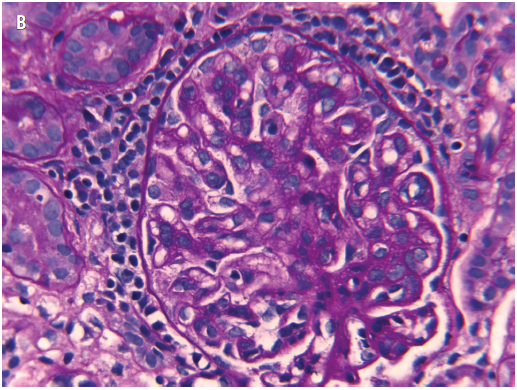

Figure 4. A, H&E stain of a representative field of the renal biopsy sample, with a glomerulus showing an increase in mesangial and endocapillary cells. B, Periodic acid-Schiff stain of the renal biopsy sample highlighting excess intercapillary amorphous matrix and thickened basement membranes.

Results of a renal biopsy, performed to evaluate the etiology of his nephrotic syndrome that was unresponsive to corticosteroids, revealed IgA nephropathy (Figures 4-6). He continued to have significant proteinuria, despite prednisone therapy and the clinical resolution of his celiac enteropathy.